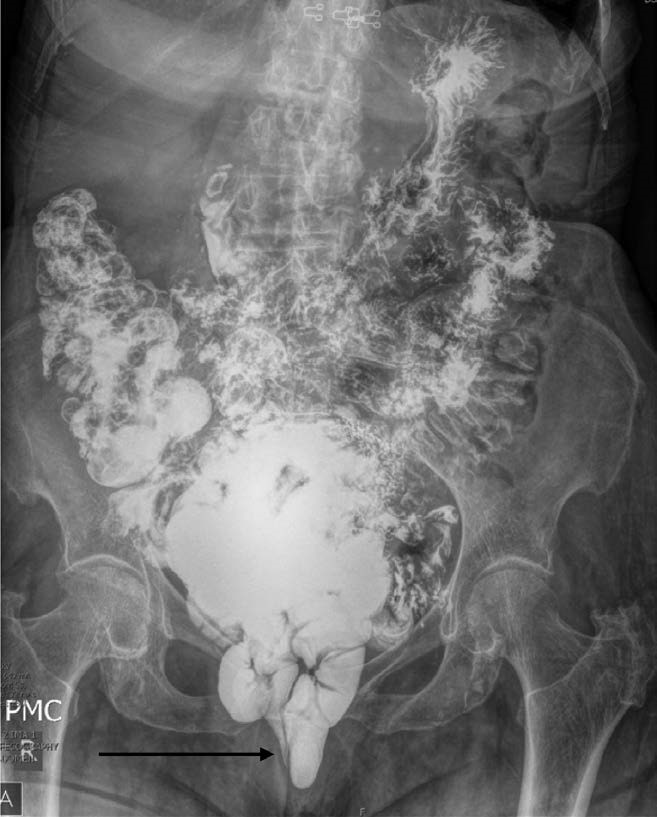

Coaching and support should continue throughout the process of image acquisition to assure patients push hard and try to expel the contrast despite their embarrassment. “Good effort” to empty the contrast should be defined as either complete rectal emptying during the examination, or at least 3 attempts to evacuate. Each attempt should last a minimum of 30 seconds (if unable to fully empty the rectum). If patients do not defecate after 3 tries, they should be asked to expel in the privacy of a bathroom and then have repeat radiographs to see if they were able to evacuate the contrast in the bathroom. In the cases when patients are successful in evacuating in the bathroom but not during the test, their defecatory effort should be labeled as either “poor” or “moderate,” depending on the level of rectal emptying achieved during the test. The emphasis on effort is demonstrated by these images that demonstrate additional pathology as effort is increased (Fig. 1).

The expert panel debated on the routine use of smallbowel contrast for FD. The proponents for the routine use of small-bowel contrast argued that opacification of small bowel allows for identification of any small-bowel herniation. Small-bowel contrast can add to the anatomical information fluoroscopy can provide and can be considered if the clinical scenario warrants it. The small bowel can enter the rectovaginal space (enterocele), or the rectum and the vagina (prolapse). All of these are substantially easier to identify when the small bowel is visible (Fig. 3). Additionally, cephalad displacement of the opacified small bowel can be seen in the setting of pelvic masses. In some instances, abnormalities such as enterocele can be suggested based on the scout images when small-bowel contrast is utilized (Fig. 4). However, members of the consortium against routine use of small-bowel contrast argued that the content of a cul-de-sac hernia was not relevant to surgical or clinical decision making. It was felt that, regardless of its content (small bowel, sigmoid colon, or omentum), the patient with any type of cul-de-sac hernia would undergo the same treatment. A cul-de-sac hernia can be identified without small-bowel contrast by observing the presence of a wide separation between the vagina and the rectum (Fig. 5). Experts argued that the addition of contrast extended the length and the discomfort of the study, especially given the possible difficulties in expelling barium from the GI tract in patients with added slow-transit constipation. Weighing these pros and cons, the consortium experts voted against routine use of small-bowel opacification, but with a very narrow margin, and with the caveat that bowel contrast could certainly be added to standard radiological protocols per local practice patterns or at the request of referring providers when this additional anatomical information is useful clinically.